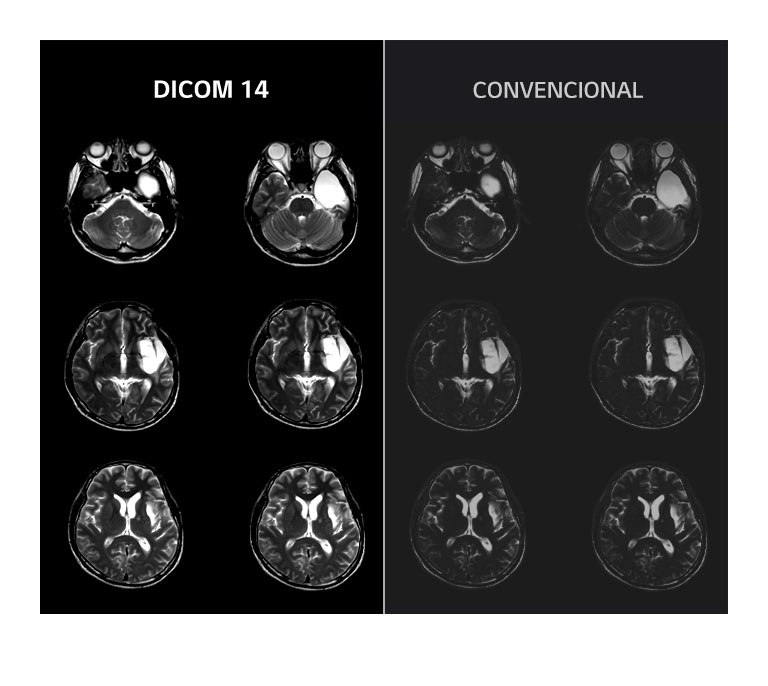

Calidad de imagen precisa

diagnóstico preciso de las imágenes médicas de la TC y la Angiografía, ya que le permite

a los médicos distinguir incluso los pequeños detalles con facilidad.